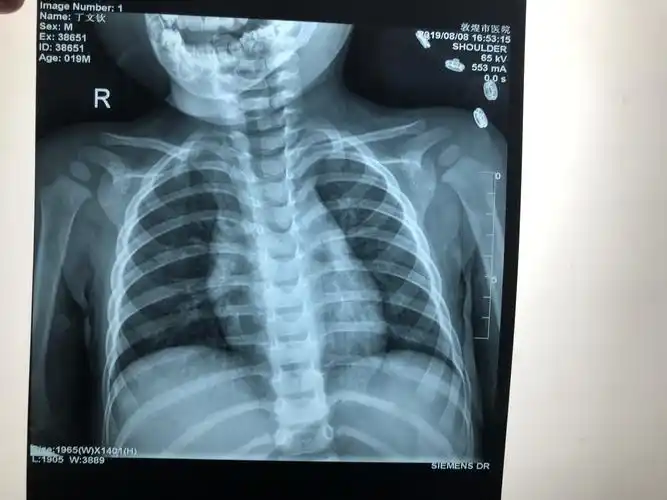

锁骨骨折

一岁半小儿锁骨骨折治疗一例.